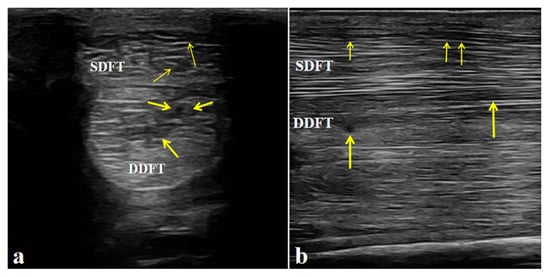

4.2.3. Post-Treatment Ultrasonographic Examination

After completing the medication combined with LIPUS-assisted therapy, ultrasonographic examination revealed marked improvement in the overall echogenicity of the affected SDFT and DDFT. Both tendons exhibited uniformly increased echogenicity, with no diffuse hypoechoic areas or regions of heterogeneous echotexture within the tendon substance. The internal homogeneity had become comparable to that of the contralateral healthy tendons. In the sagittal scans, the normal parallel, fibrillar echotexture was largely restored, showing well-organized, continuous fibers aligned with the longitudinal axis of the tendon, without evidence of disruption or fiber-pattern irregularity (Figure 6).

Figure 6. Post-treatment ultrasonographic images of the affected horse. (A,B) Increased echogenicity and uniform fibrillar alignment of the superficial digital flexor tendon (SDFT) and deep digital flexor tendon (DDFT), without fibrosis or adhesions. Arrows indicate the repaired areas of the tendon post-treatment.